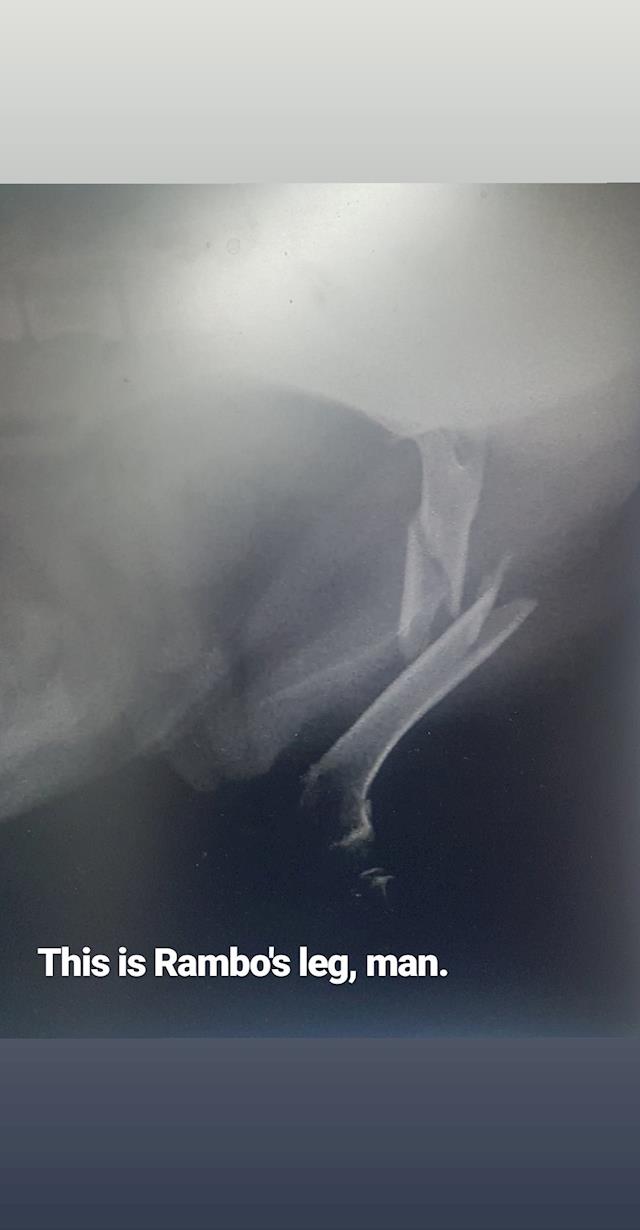

Our Rambo Needs Surgery

• Our Rambo is out of surgery!

It went really well, I just got off the phone with the amazing team at Mangere Vet Clinic & Onehunga Vet and Pet Supplies who've done a brilliant job of fixing up our Ramby.

The cost of the surgery comes to $1,271.60 so we are very much on track to getting it together and getting him home. Some update pics from the vets 😭🙌 thanks again to every who has donated or shared, it means the world to us and of course to our Rambo (though he may not show it, unless you have treats).